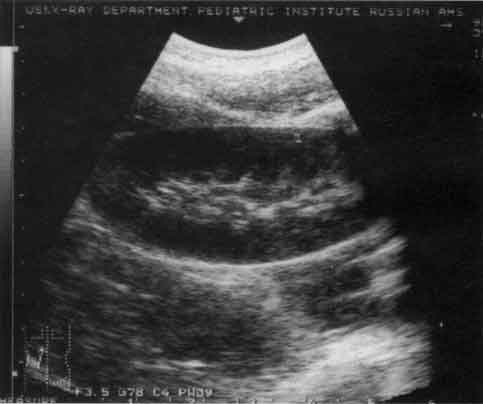

Диагностика болезни Гиршпрунга и долихосигмы сходна с рентгенологической. В первом случае определяется значительное расширение кишки (воронка) выше ее суженного отдела, имеющего выраженное утолщение стенок. Во втором обнаруживается одна или несколько дополнительных петель сигмовидной кишки, как правило, с нормальными стенками. Преимущество в этих случаях УЗИ перед рентгенографией состоит в его значительно большей доступности, простоте применения, отсутствии ионизирующей радиации. Вместе с тем метод эхографии является как бы дополнительным, скрининговым методом, на основании результатов которого решаются вопросы дальнейшей диагностической и/или лечебной тактики для конкретного ребенка (рис. 11).

Рис. 11. Эхограмма прямой (R) и сигмовидной (S) кишки при болезни Гиршпрунга.